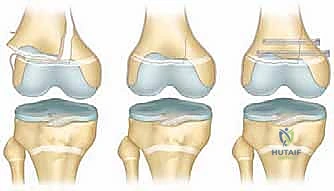

* استخدام البراغي المجوفة (Cannulated Screws): في كسور (سالتر-هاريس النوع الثاني)، يتم إدخال البراغي عبر "شظية ثورستون-هولاند" العظمية إلى الكردوس، بشكل موازٍ لصفيحة النمو دون لمسها أو اختراقها أبداً. هذه التقنية تتطلب مهارة مكانية (Spatial awareness) عالية جداً يمتلكها الدكتور هطيف.

4. استخدام تقنيات المناظير (Arthroscopy 4K)

في الكسور التي تمتد لداخل المفصل (النوع الثالث والرابع)، قد يستخدم الدكتور هطيف منظار الركبة بدقة 4K لرؤية السطح المفصلي من الداخل والتأكد من تطابقه بنسبة 100%، وإزالة أي شظايا غضروفية حرة قد تعيق حركة الركبة مستقبلاً.

5. إغلاق الجرح التجميلي (Cosmetic Closure)

إدراكاً منه للأثر النفسي للندبات على الأطفال، يستخدم الدكتور هطيف تقنيات الجراحة المجهرية والخيوط التجميلية القابلة للامتصاص لإغلاق الجروح بأفضل شكل